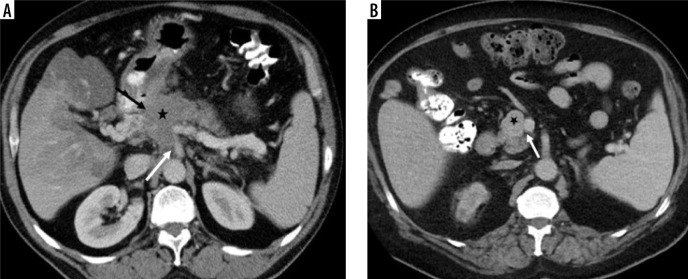

Results: There was no difference between the groups in terms of age, gender, tumour localisation, and internal structure (p = 0.23, p = 0.81, p = 0.19, and p = 0.94, respectively). Qualitative features significantly differed in terms of tumour margin feature, visual tumour density, presence of cystic component, and presence of necrosis (p = 0.01, p = 0.0001, p = 0.002, and p = 0.004, respectively). Tumour size, Tmden, Tmden/VPden, and Tmden/PanPden showed differences between groups (p = 0.0001, p = 0.002, p = 0.0001, p = 0.0001, respectively). The presence of cystic density in PDAC patients differed according to grade (p = 0.01).

Conclusions: While ill-defined irregular margins, hypodense visual tumour density, no cystic component, low value of Tmden, and low ratios of Tmden/VPden and Tmden/PanPden indicate PDAC, regular margins, iso-or hyperdense visual tumour density, cystic component, high value of Tmden, and high ratios of Tmden/VPden and Tmden/PanPden indicate PNET. SC can be differentiated from them by containing necrosis and reaching larger sizes. The presence of a cystic component in PDAC patients indicates high grade.